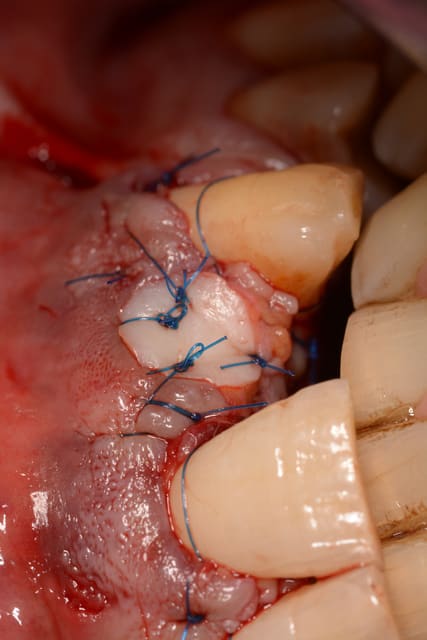

extraction curetage, pose d'un bloc biobank cortico-spongieux et poudre d'os biobank, membrane at collagene et patch palatin pour fermer le lambeau.